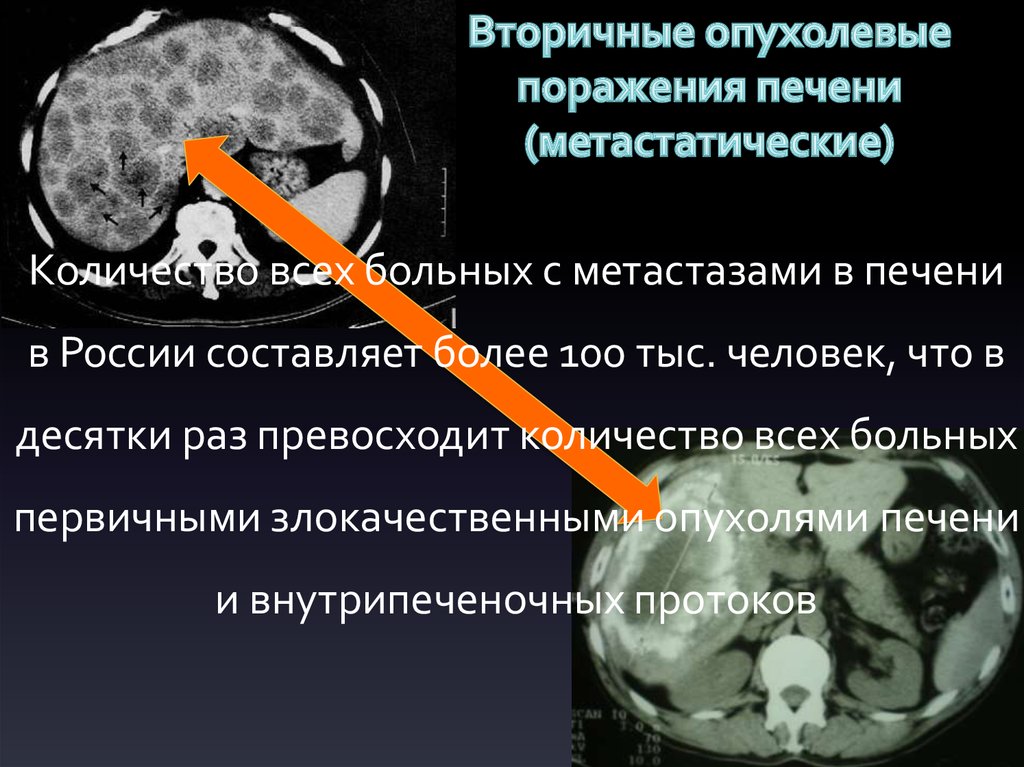

Метастатические поражения печени в ультразвуковом изображении характеризуются